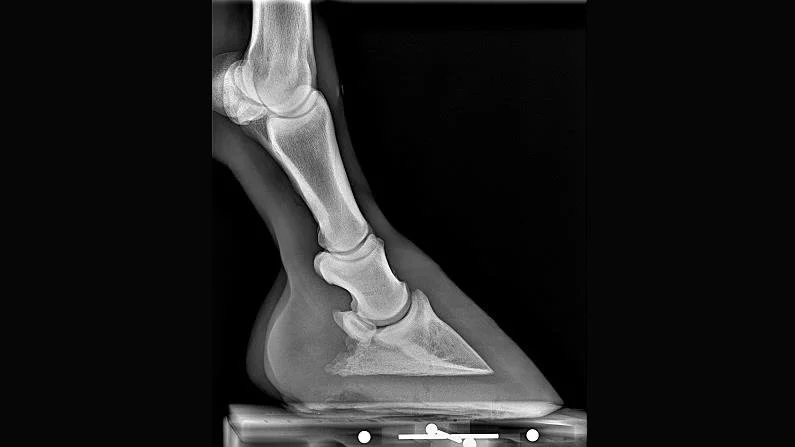

Metron-IQ will automatically and impartially measure the hoof and lower leg in the Lateral and DP radiographs. For those two views a total of 13 measures will be presented. A report suitable to give to your clients is automatically produced (see sample here).

What measurements are made from a Lateral radiograph? See definitions and statistics for front hooves here, and for hind hooves here.

* Hoof Lateral Radiograph

For those 6 images, measurements are automatically performed, and documented in the report. Example reports for these 6 image types can be seen on our ‘Scope’ page. Some image types result in 2 or more pages in the report. Reports can be edited by the user: pages deleted, pages re-ordered, and results from the AI: image labelling, rotation, or mark-up — can be edited if needed.